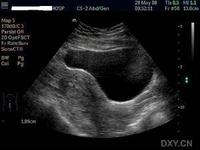

異位妊娠